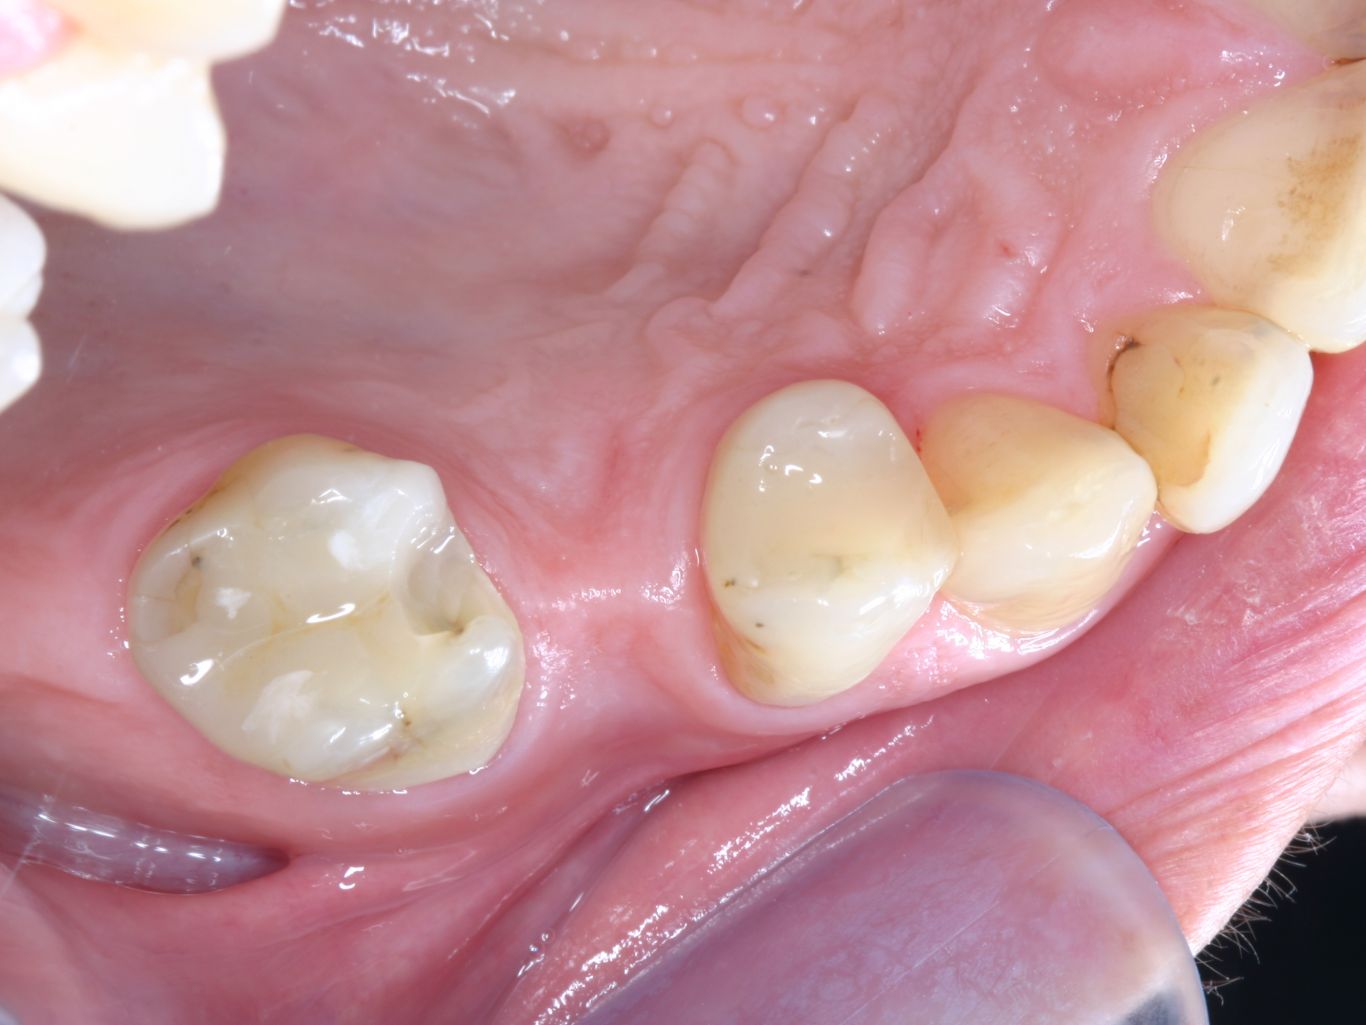

Best Material For Posterior Bridge . No matter how long the bridge you need in the posterior region, solid zirconia can be a great choice. It is very durable and looks great. The choices were limited with cost to. Gordon christensen gives a review of the different types of dental restorative materials on the market and discusses the clinical strengths and weaknesses of each regarding their usefulness as material for posterior crowns. The results of this study support the evidence that zirconia is an appropriate material for anterior and posterior bridges. To help demystify the world of crown and bridge material selection, let's explore the most popular options along with their respective strengths and weaknesses. Zirconia ht is made from a stronger material than that of pfm restorations but still has a natural translucency and excellent esthetics. There were instances of less than ideal. Porcelain, zirconia, or ceramic bridges are popular. Most parameters were rated “a” at all visits. Discuss with your dentist the best materials to ensure a natural appearance and optimal comfort.

Best Material For Posterior Bridge Discuss with your dentist the best materials to ensure a natural appearance and optimal comfort. The choices were limited with cost to. There were instances of less than ideal. The results of this study support the evidence that zirconia is an appropriate material for anterior and posterior bridges. No matter how long the bridge you need in the posterior region, solid zirconia can be a great choice. Zirconia ht is made from a stronger material than that of pfm restorations but still has a natural translucency and excellent esthetics. Most parameters were rated “a” at all visits. To help demystify the world of crown and bridge material selection, let's explore the most popular options along with their respective strengths and weaknesses. It is very durable and looks great. Discuss with your dentist the best materials to ensure a natural appearance and optimal comfort. Gordon christensen gives a review of the different types of dental restorative materials on the market and discusses the clinical strengths and weaknesses of each regarding their usefulness as material for posterior crowns. Porcelain, zirconia, or ceramic bridges are popular.